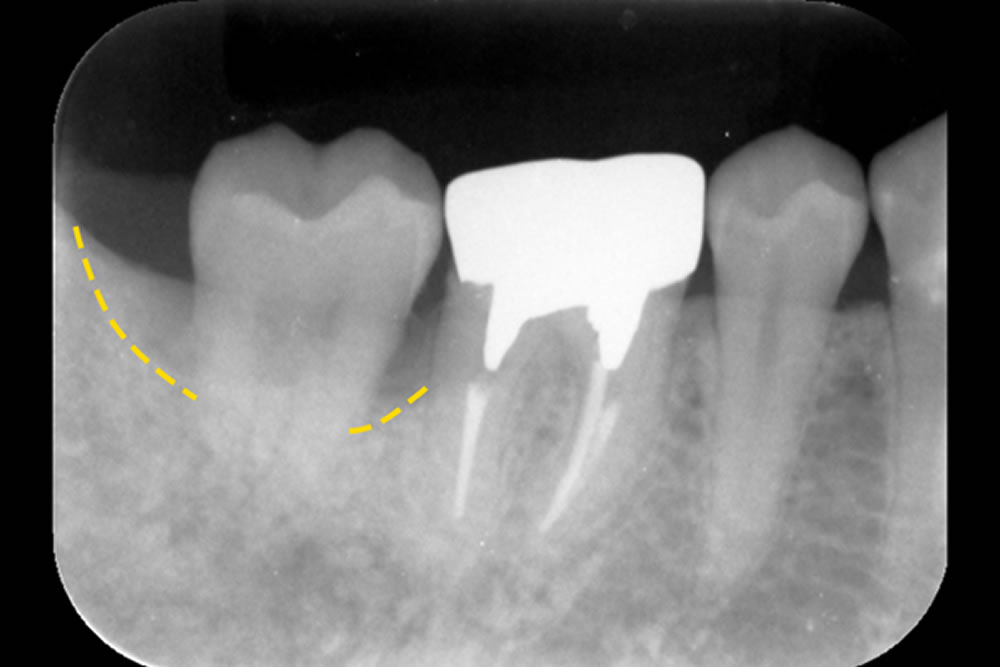

こちらの患者さまは、右下の奥歯(第2大臼歯)に歯の根の内部(神経)と歯の周囲の組織(歯周組織)の両方に問題がある複雑な状態でした。治療は、まず根の中の感染をしっかり取り除く「根管治療」を最初に行い、その効果を確認した後、歯周組織を回復させる再生治療を実施しました。

特に、隣り合う第1大臼歯との間では、血液の流れを妨げずに治癒を促すため、切開の方向や位置を工夫して手術を行いました。術後2年半が経過しましたが、治療部位は安定しており、良好な状態を保っています。